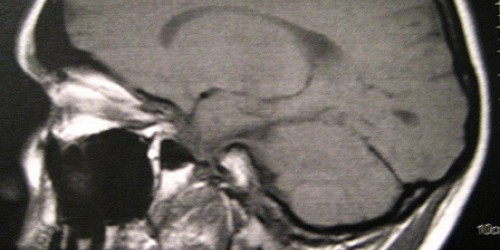

My friend has been suffering from brain tumor, called schwannomas. It is some kind nerve tumor. He is going to have surgery. He already lost hearing. I am very worried about him. He has not being well for a long time. I am not sure how I can help him. I don’t understand this condition. I would like to get some detail explanation about what the schwannomas is. Please, is there anyone who can tell me?

I am sorry about your friend. I can give you some information about Schwannomas. I thought that is only congenital condition, but recently I read that anyone can develop these tumors. Schwannomas tumors come from the cells that form a protective sheath around the body's nerve fibers. They usually appear as a single tumor, benign and surgically removed when is possible. They rarely multiply. Hearing loss is a common symptom, because one of the more common forms of this tumor affects the eighth cranial nerve, which contains nerve cells important for balance and hearing.